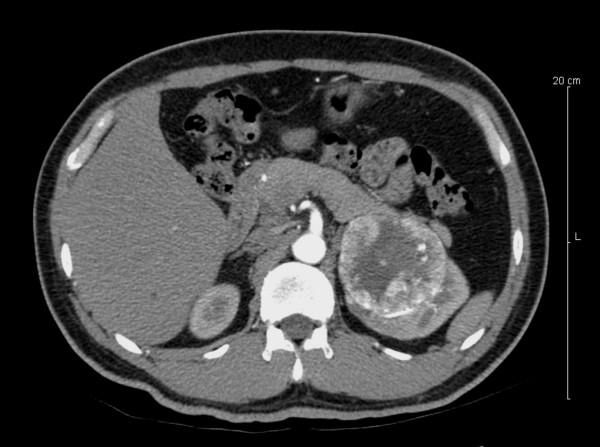

We present in this case report a ciliated hepatic foregut cyst found incidentally in the setting of renal carcinoma. The patient was a man known to have a large renal mass, assumed to be cancer, and a liver mass suspicious for metastatic disease. This liver mass was cystic and upon further analysis showed ciliated epithelial lining. We describe the gross and histological appearance, as well as a brief discussion of ciliated hepatic foregut cysts.

我们在此病例报告中呈现一例在肾癌背景下偶然发现的纤毛肝前肠囊肿。患者为一名男性,已知有一个大的肾肿物,推测为癌症,还有一个肝脏肿物怀疑为转移性疾病。这个肝脏肿物为囊性,进一步分析显示有纤毛上皮内衬。我们描述了大体和组织学表现,并对纤毛肝前肠囊肿进行了简要讨论。